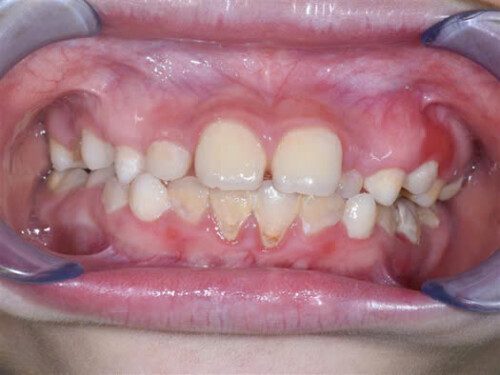

- Gây chảy máu lợi, sưng lợi, tụt lợi

- Ảnh hưởng tới thẩm mỹ khi nói, cười vì cao răng có màu thường đậm hơn so với màu răng. Đặc biệt ở những người thường xuyên uống cà phê, hút thuốc lá, cao răng thường có màu đen.